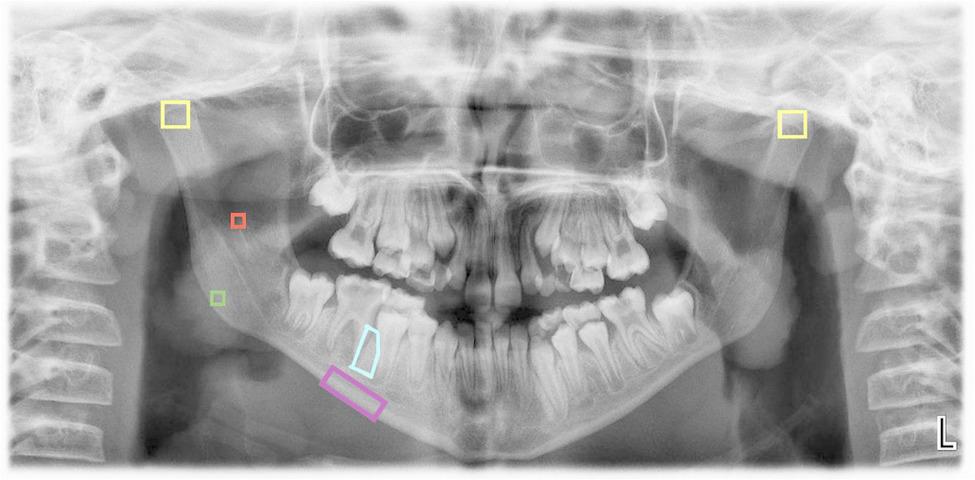

In each radiograph provided by the patients, five regions of interest (ROIs) were selected (Fig. 1):

Fig. 1.

ROIs selected using the ImageJ application

ROI 1: A 25x25-pixel square in the trabecular bone at the geometric center of the mandibular ramus.

ROI 2: A 25x25-pixel square in the trabecular bone at the geometric center of the mandibular angle.s

ROI 3: A 60x60-pixel square in the trabecular bone at the cortical boundaries of each condyle (right and left), with the upper vertices positioned as high as possible.

ROI 4: A rectangle in the basal cortical bone, starting distal to the mental foramen and extending to the distal edge of the mesial root of the first permanent molar, encompassing only the mandibular cortex. This measurement is performed using the polygon tool in the ImageJ software.

ROI 5: A polygonal region within the trabecular bone at the level of the interradicular septum, between the mesial root of the first permanent molar and the distal root of the second permanent premolar; or, alternatively, the distal root of the second primary molar, depending on the patient’s developmental stage. The ROI extends from the furcation of the first permanent molar to its apex. In cases where the apex remains open, the distal limit is defined by the end of the dental follicle, whether corresponding to the first permanent molar or the developing germ of the second premolar. In younger patients in whom the first molar has not yet erupted, the ROI is proportionally smaller, although its anatomical boundaries are preserved. This measurement was performed using the polygon selection tool in ImageJ software. Notably, this region of interest was specifically designed for the present study and has not been previously described in the literature.